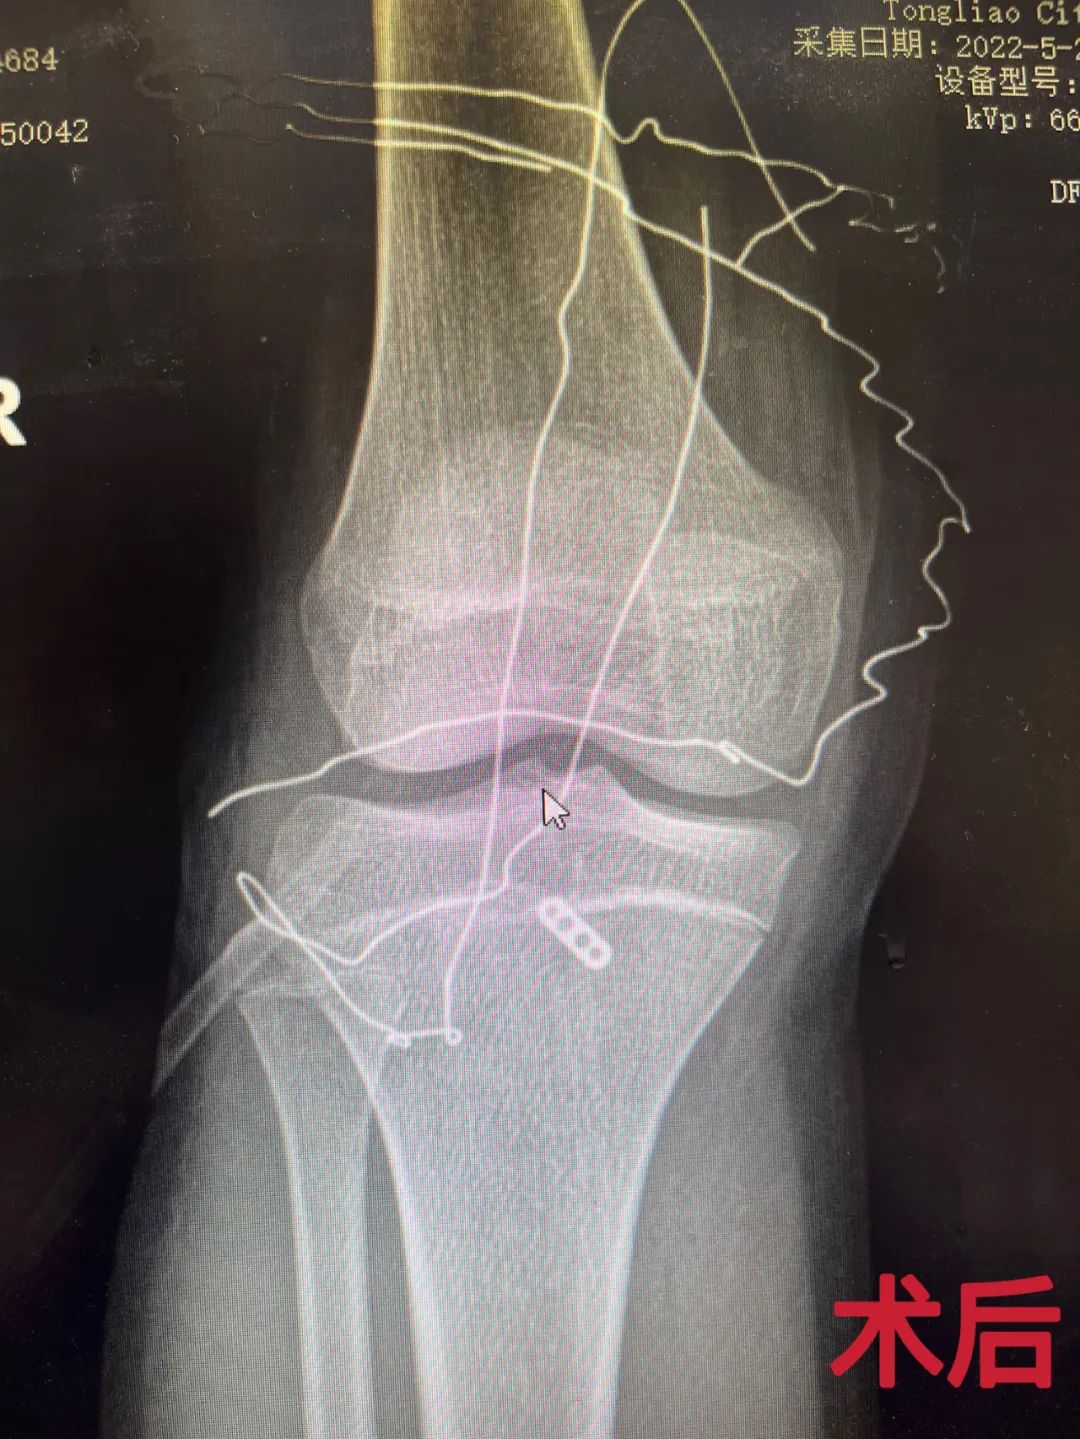

我院骨三科主任兰荫梧及主治医师兰忠煜即刻制定治疗方案,在与患者和家属充分沟通后,兰忠煜医生第一时间为患者实施关节镜下右胫骨髁间嵴骨折内固定术,整台手术在医生有条不紊地操作下顺利完成。术后,患者在我院骨三科全体医护人员的精心护理下康复出院。